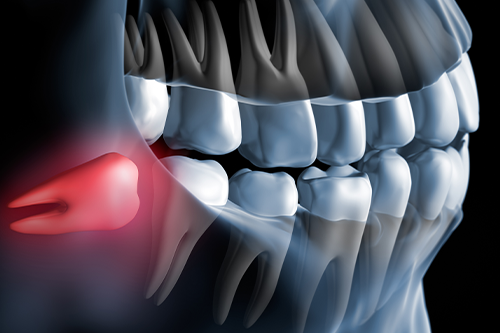

問題が起きやすい原因のひとつは、顎のスペース不足にあります。現代人は食生活の変化によって顎が小さくなる傾向にあり、最後に生えてくる親知らずが収まりきらず、斜めや横向きに生えてしまうケースが少なくありません。

斜めに生えた親知らずは手前の歯(第二大臼歯=親知らずのひとつ手前の奥歯)を圧迫したり、歯ブラシが届きにくい構造となるため、虫歯や歯周病のリスクが高まります。また、歯と歯茎の間に食べかすが溜まりやすく、炎症を繰り返しやすい環境になります。

横向きに生えた親知らずのイメージ